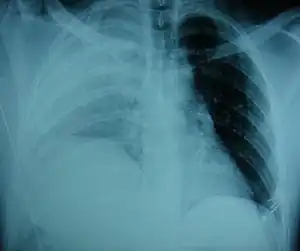

Selected image –